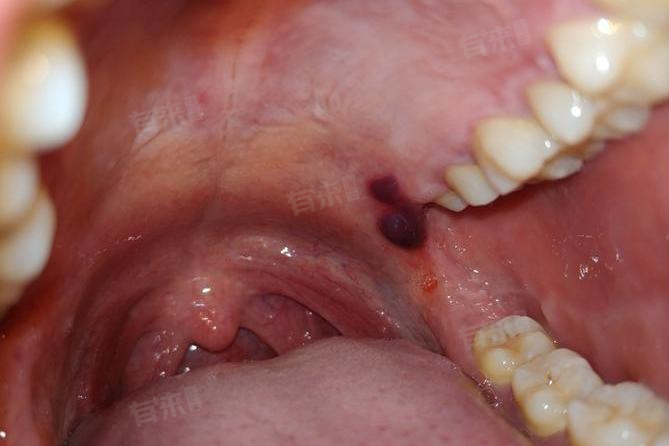

2、创伤性血疱:创伤性血疱可能由于外力挫伤或误咬颊、舌黏膜造成,也可能由于吃过热、过硬的食物导致口腔黏膜受损。血疱一般较大,疱壁很薄,容易破裂,出血后会出现红色的疱疹,可能导致吞咽困难。通常会很快痊愈,但如果有继发性的感染,就可能出现溃烂或溃疡。

4、牙龈瘤:牙龈瘤是牙龈上生长的局限性增生物,可能表现为柔软的红紫色包块,极易出血,有时可能被误认为是牙龈长血泡。

5、黏膜类天疱疮:黏膜类天疱疮是一种自身免疫性疾病,可能导致口腔黏膜出现张力性水疱和糜烂。患者如果免疫功能异常,可能会引起类天疱疮,导致嘴巴里长红色血泡,此种情况通常还伴有明显的瘙痒。